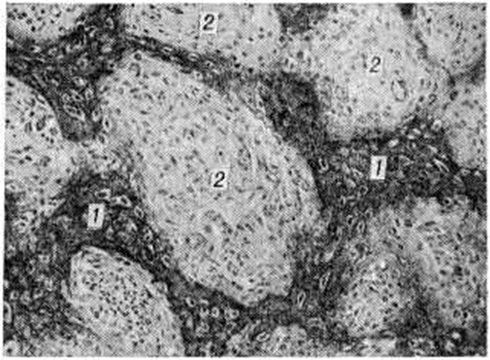

Микроскопически при врождённом и позднем Остеогенез несовершенный обнаруживают однотипные изменения: недостаточное развитие основного вещества (рисунок 2) во всех костях, развивающихся как на хрящевой, так и на соединительнотканной основе. Эпифизарные хрящи имеют нормальную структуру, зона предварительного обызвествления хряща и зона его рассасывания имеют обычные контуры, однако в очагах петрификации отмечается недостаточное костеобразование. Поэтому в субхондральной зоне образуются большие пространства, заполненные нежноволокнистой тканью. На первичных костных структурах в области метафизов в дальнейшем происходит слабое наслоение костного вещества последующих генераций, поэтому сеть костных пластинок приобретает широкопетлистый характер. Недостаточное развитие костного вещества отмечается и в диафизах (в зонах надкостницы и эндоста). Поэтому корковое вещество представляется чрезмерно тонким и как бы изъеденным широкими центральными (гаверсовыми) каналами. Корковое вещество диафиза длинных трубчатых костей достигает 1 —1,5 миллиметров, на большем протяжении оно состоит лишь из генеральной пластинки, отграничивающей костномозговую полость от периоста. Костномозговые полости—с тонкими костными перекладинами, образующими широкопетлистую сеть, открывающуюся во многих участках под периостом (смотри полный свод знаний Остеопороз).

Кости крыши черепа при врождённом Остеогенез несовершенный образованы соединительнотканной оболочкой, содержащей различной величины островки обызвествления и тонкие костные пластинки с широкими пространствами между ними, заполненные нежноволокнистой соединительной тканью. Костные перекладины и их отломки окружены правильно сформированными остеобластами. При позднем Остеогенез несовершенный отмечается чрезвычайное истончение костей крыши черепа, микроскопически имеющих крупноячеистую структуру с весьма слабо развитыми наружными пластинками. Пространства между костными перекладинами заполнены нежноволокнистой соединительной тканью и островками миелоидного костного мозга. В губчатом веществе длинных и плоских костей также отмечается уменьшение массы костной субстанции, а костномозговые полости заполнены жировым и миелоидным костным мозгом. В зонах старых переломов обнаруживаются значительные разрастания фиброзно-ретикулярной ткани, представляющей собой эндостальные пролифераты; наблюдается также значительное разрастание волокнистого и гиалинового хрящей. В области несросшихся переломов длинных трубчатых костей (ложные суставы) отмечается разрастание фиброзной ткани, связывающей резко атрофичные с изъеденными краями костные отломки. Суставные хрящи бедренной и других костей при Остеогенез несовершенный значительно тоньше нормальных, поверхность их остаётся гладкой. Микроскопически в них отмечается почти полное отсутствие хондромукоида (смотри полный свод знаний Хондромукопротеиды). С помощью методов микрорадиографии, дифракции рентгеновских лучей и микроскопии в поляризованном свете выявляется дезорганизация коллагена, а также неупорядоченное распределение в нем кристаллов минеральных солей.